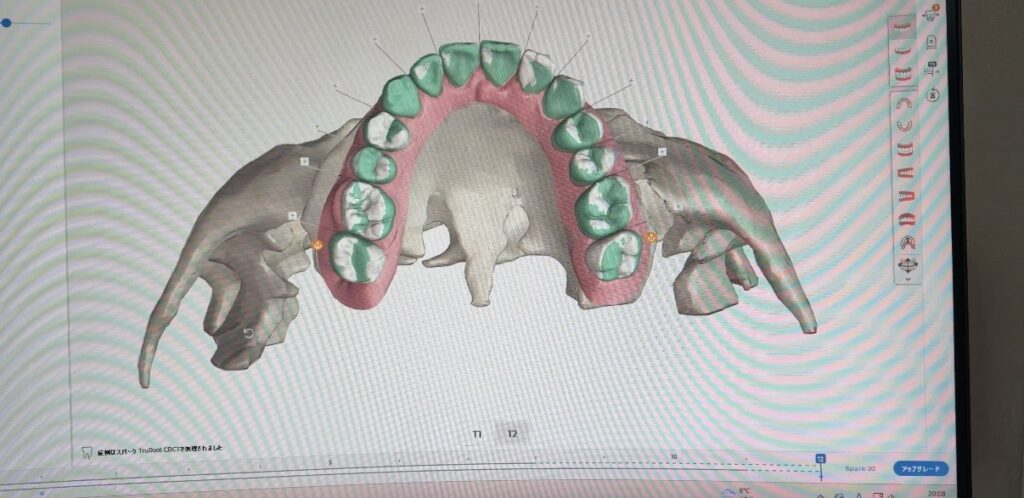

✔️ 精密なデジタルシミュレーションにより、ゴールをイメージしやすい治療